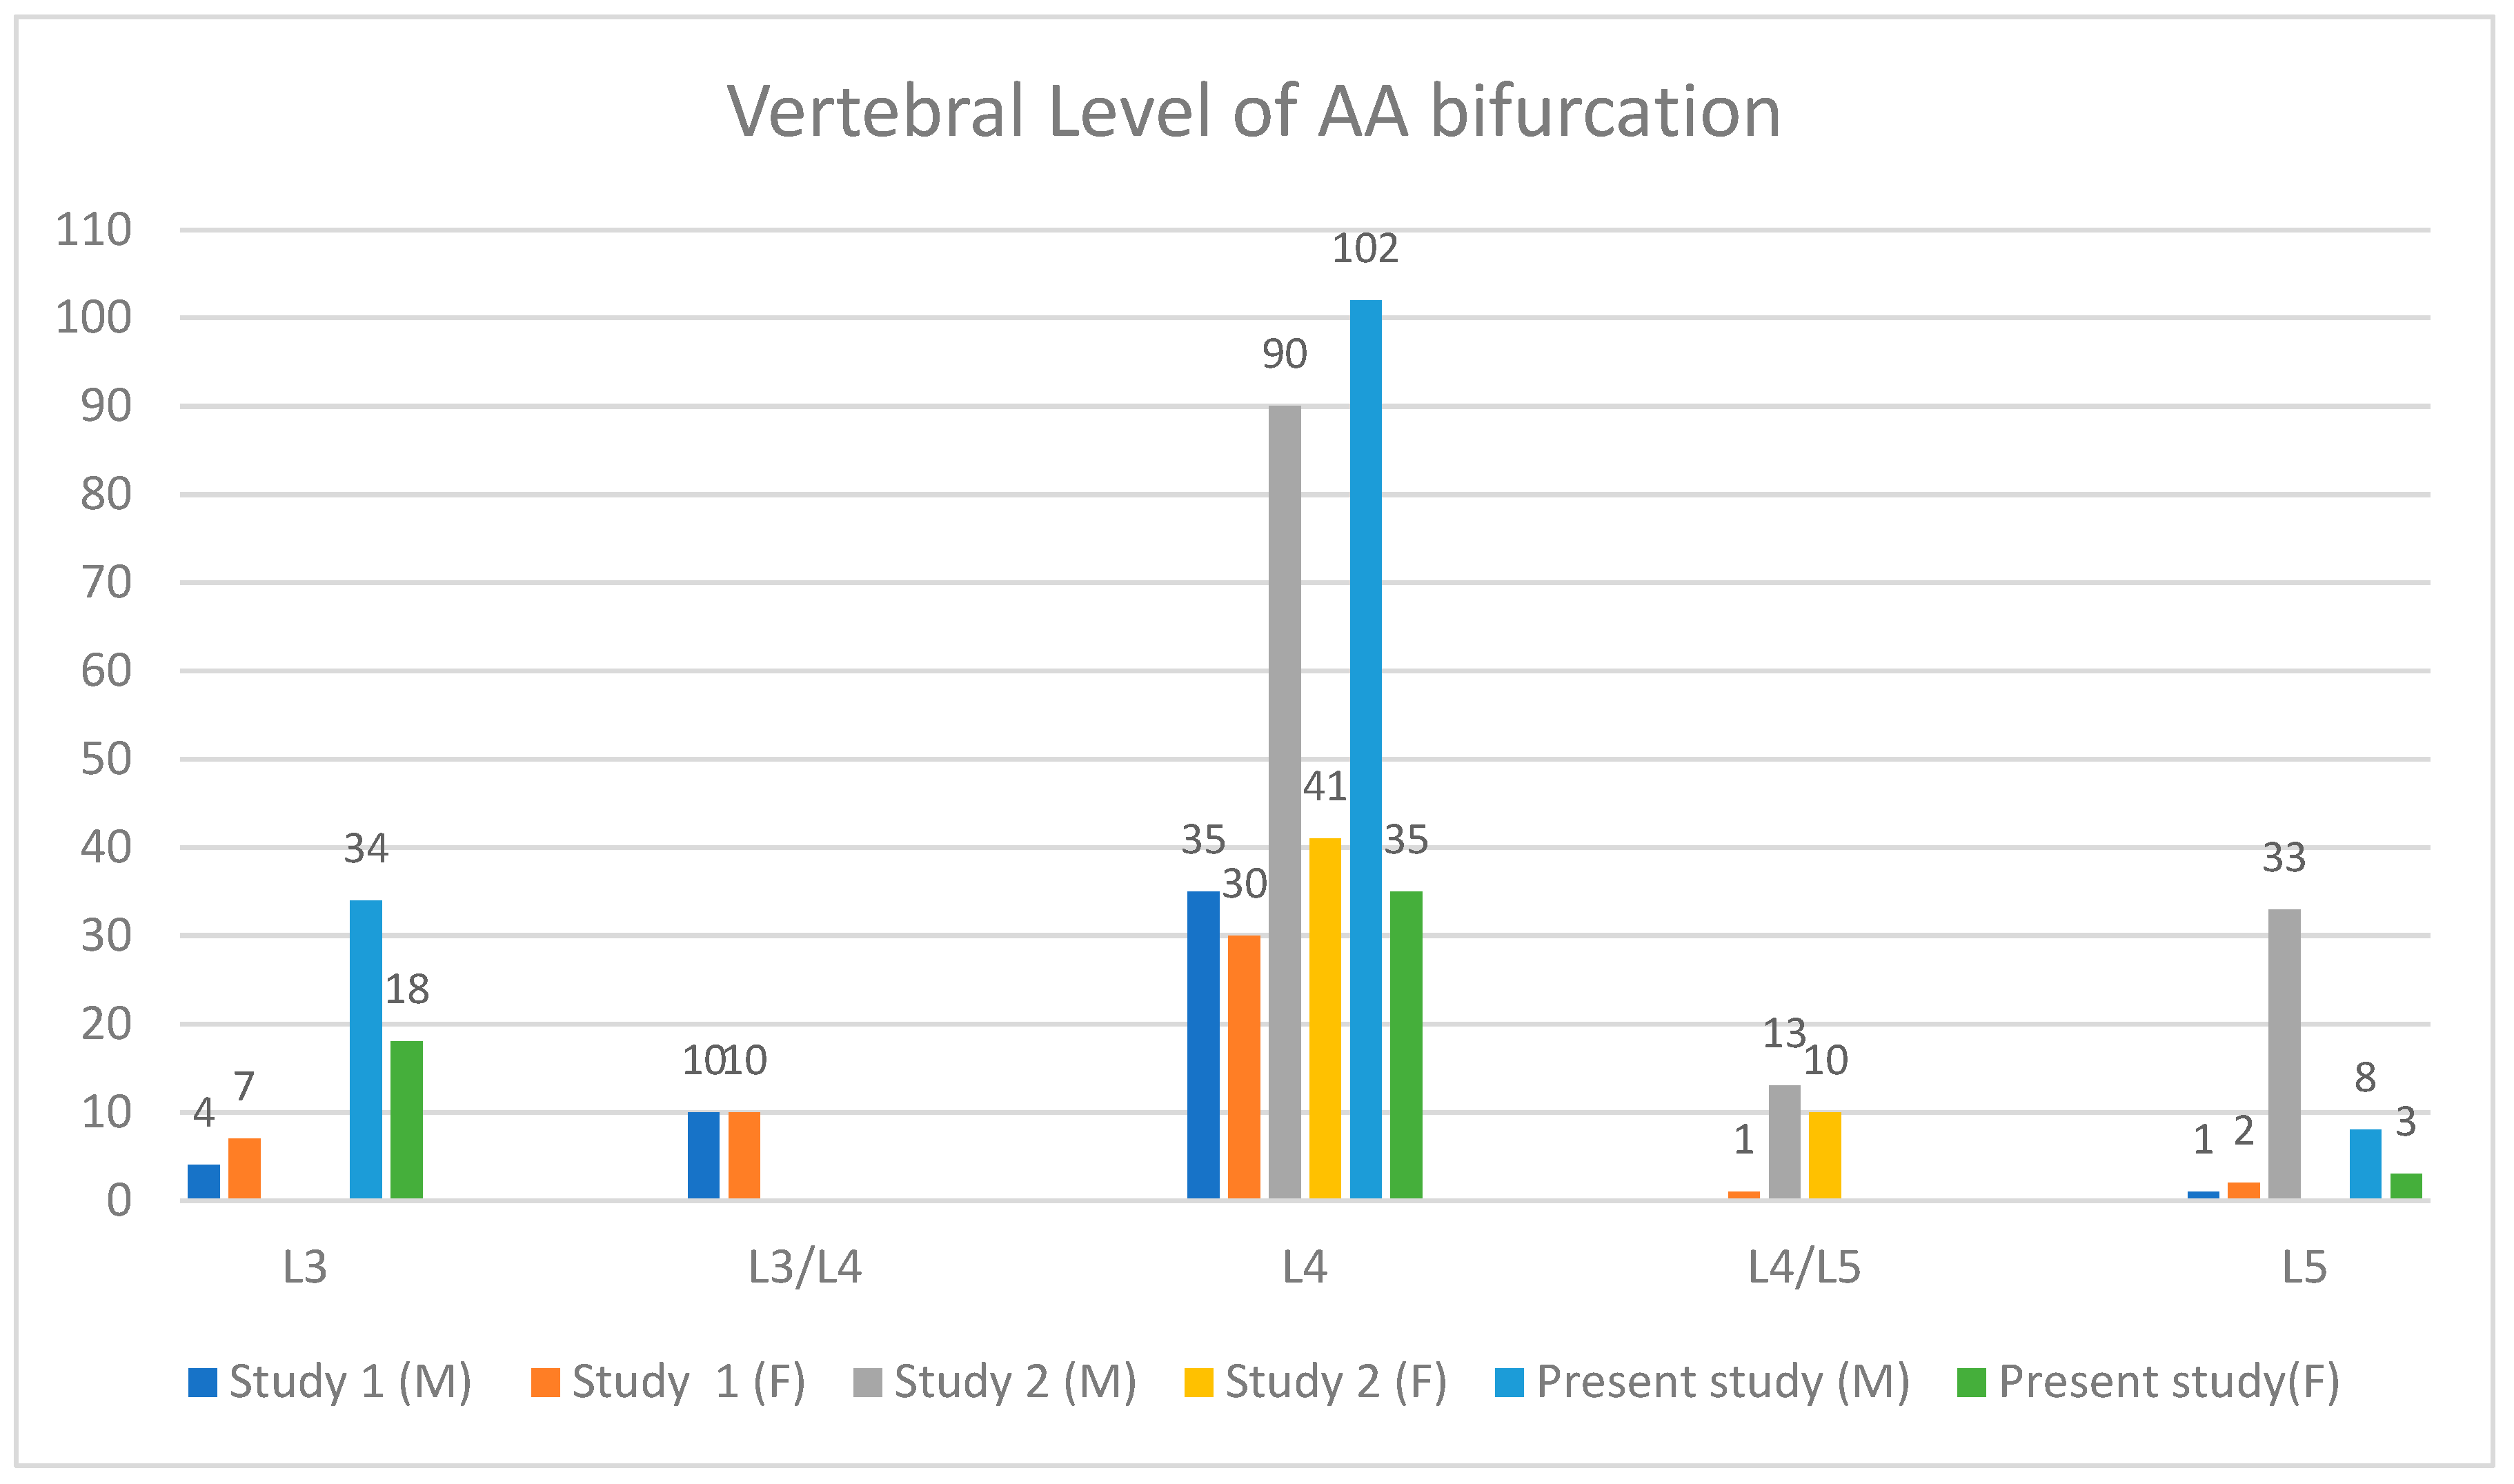

| Vertebral Level | Males | Females |

|---|---|---|

| L3 | 34 (23.61%) | 18 (32.14%) |

| L4 | 102 (70.83%) | 35 (62.50%) |

| L5 | 8 (5.56%) | 3 (5.36%) |

| Total | 144 (100%) | 56 (100%) |